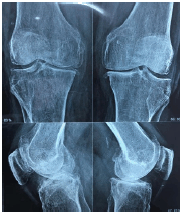

Paciente mulher com 68 anos, IMC 32, apresenta dor crônica em joelhos, com piora progressiva, interferindo na marcha. Ausência de outras queixas articulares. A radiografia simples em incidências anteroposterior e perfil são demonstradas na imagem abaixo.

Diante das características clínicas e radiográficas desta paciente, analise as proposições abaixo e responda o que se pede.

I- A diminuição acentuada do espaço articular sugere o diagnóstico de artrite reumatoide, devendo iniciar o uso de glicocorticoide e metotrexato.

II- A dor certamente não provém da cartilagem, visto ser aneural, estruturas bem inervadas como ênteses, ligamentos e osso subcondral podem ter seus nociceptores estimulados, quer por tração mecânica, quer por mediadores algogênicos como prostaglandina E2, liberada localmente.

III- A obesidade constitui um fator de risco, seja pelo fator mecânico, a impor maior desgaste às estruturas articulares, seja por mediadores inflamatórios, como adipocinas, produzidas no tecido adiposo, que potencializam a inflamação local.

IV- O uso de colágeno hidrolisado tipo II está bem estabelecido como medida terapêutica, no propósito de estimular os condrócitos no restabelecimento do equilíbrio da matriz cartilaginosa e dos proteoglicanos.

V- É necessário ao médico abordar eventuais comorbidades e orientar o seu tratamento, sugerindo atendimento especializado adicional, uma vez que conviver melhor com a senescência e tratar comorbidades contribui para reduzir a perda de força muscular e do equilíbrio.

É CORRETO apenas o que se afirma em: